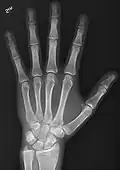

• Hand - DP and Oblique